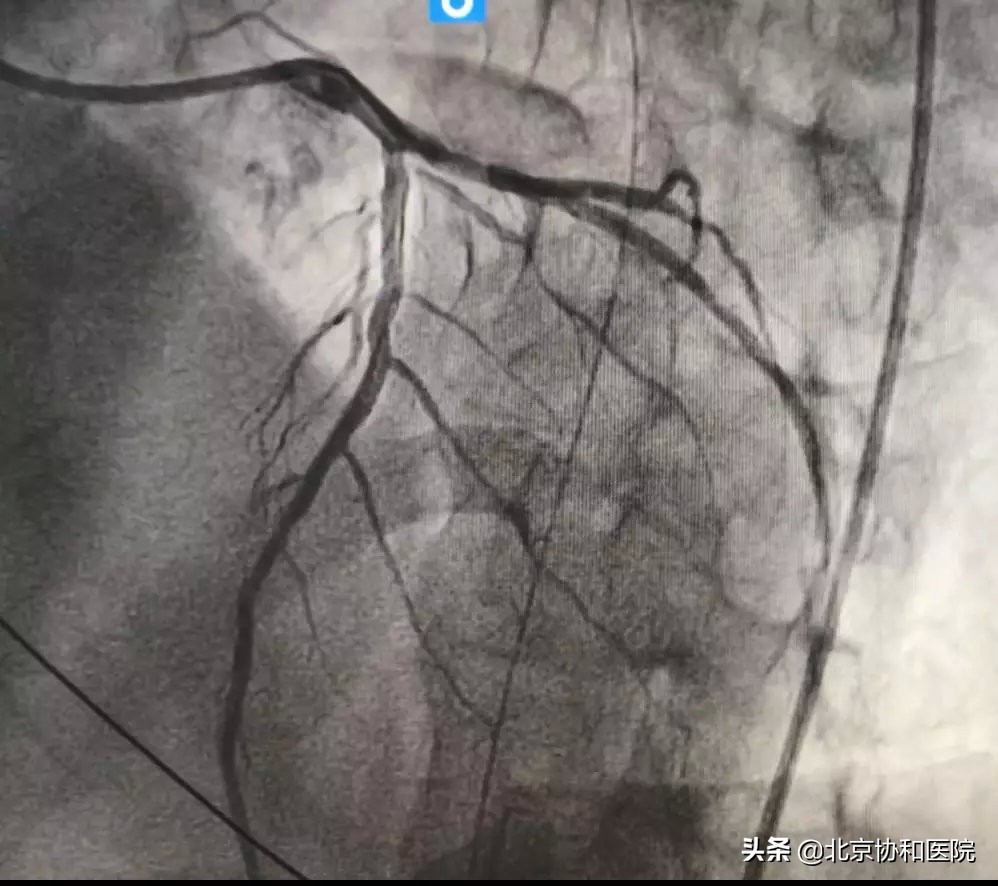

导管室准备就绪且通知转运病人。董先生在急诊科医护的陪同下被转入心内科导管室,由刘震宇医生进行急诊冠脉造影和急诊PCI(经皮冠状动脉介入术)。冠脉造影显示患者前降支近端完全闭塞,植入支架后血管恢复畅通。术后收入CCU(冠心病重症监护室病房)进一步治疗。

放置支架前(左图)后(右图)对比—前降支远端血管畅通 图/王江山